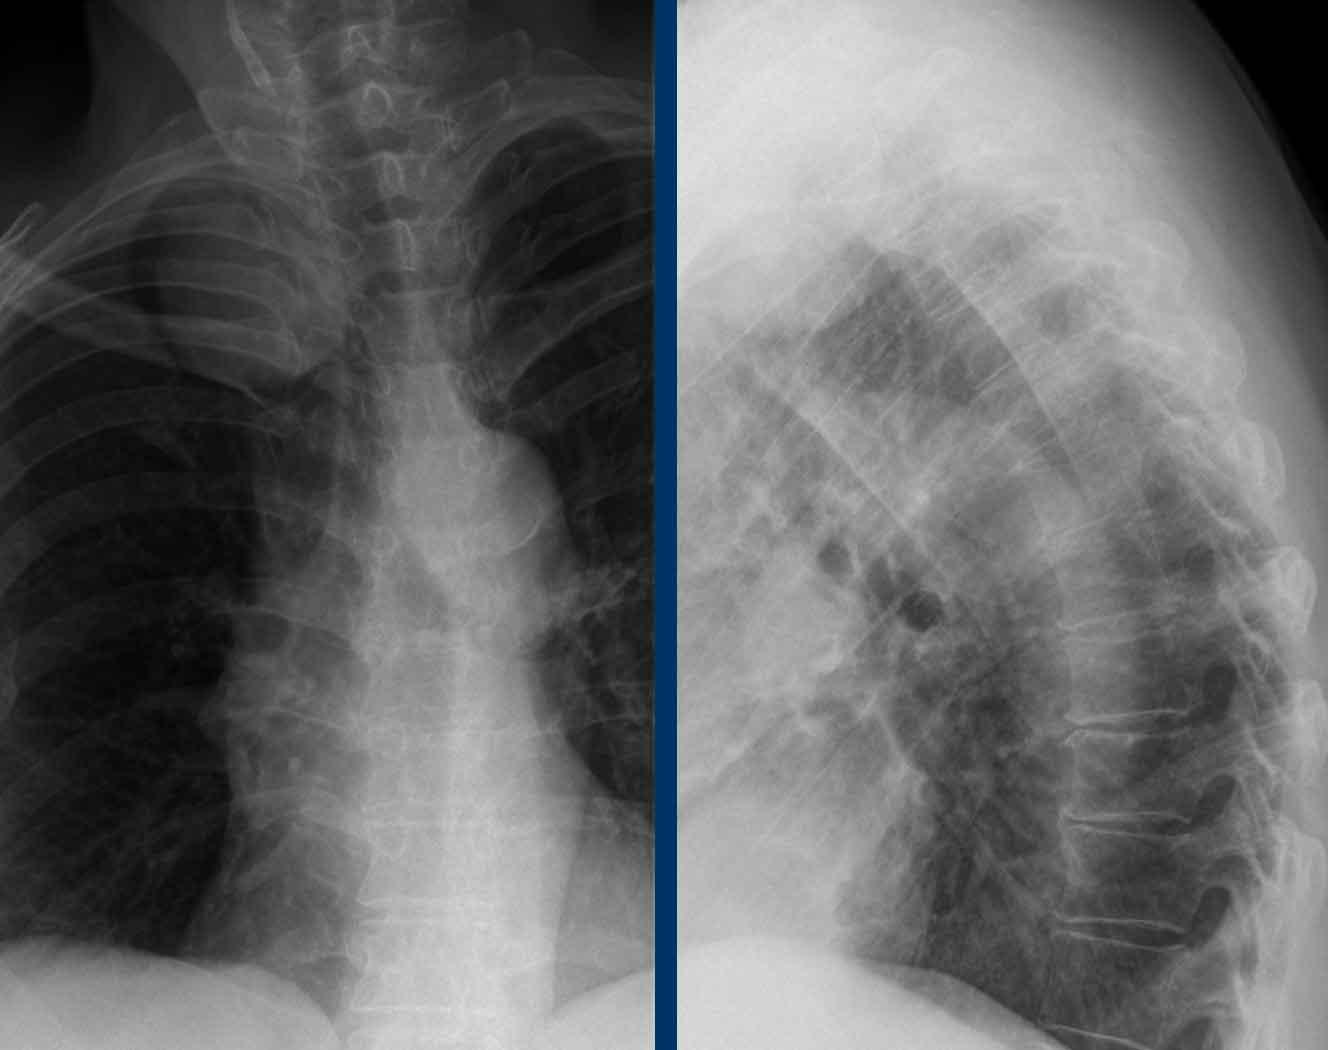

Hình ảnh của một phụ nữ 55 tuổi với triệu chứng đau vai và cổ.

Hình ảnh

X-quang cột sống cổ

và cột sống ngực cho thấy một khối u chiếu lên vùng đỉnh

phổi phải.

Dựa vào dấu hiệu cổ-ngực, khối u nhiều khả năng xuất phát

từ trung thất sau.

Chẩn đoán phân biệt

Chẩn đoán có khả năng nhất của một khối u ở trung thất sau là:

- Neurogenic tumors

(schwannoma, neurofibroma). - Lymphadenopathy.

- Neuroenteric cysts

- Meningoceles

- Extramedullary

hematopoiesis.

Nhấp vào đây để biết thêm thông tin về các khối u trung thất.

Tiếp tục với các hình ảnh tiếp theo…

Tại khám thần kinh, hội chứng Horner bên phải được phát hiện.

Đầu tiên, chụp CT được thực hiện vì nghi ngờ có thể có ác tính.

CT cho thấy một tổn thương có vỏ bao ở trung thất sau.

Không có hạch bạch huyết to.

MRI cho thấy tổn thương giới hạn rõ với tín hiệu tăng trên T2 gợi ý nang hoặc hoại tử.

Continue…

Images

The sagittal T1W image shows rim enhancement.

Kết luận

Tổn thương có hiệu ứng khối lên hạch cổ dưới bên phải và đây là nguyên nhân gây ra hội chứng Horner.

Chẩn đoán có khả năng nhất là u bao thần kinh (schwannoma) cũ.